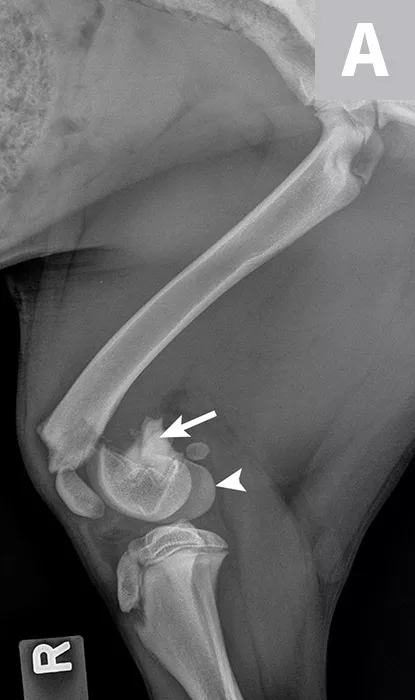

Hydromorphone (0.05 mg/kg IV) was administered for analgesia, and lateral and ventrodorsal thoracic radiographs were obtained to evaluate for thoracic trauma. Radiographic findings were within normal limits; however, lateral and craniocaudal radiographs of the right pelvic limb (Figure 1) revealed a Salter-Harris type II fracture of the distal femur with caudal and medial displacement.

Figure 1

Lateral (A) and craniocaudal (B) radiographs of this patient’s femur. A Salter-Harris type II fracture with caudal and medial displacement is present in the distal femur. The metaphyseal component (A; arrow) and the epiphyseal component (arrowhead) can be noted.